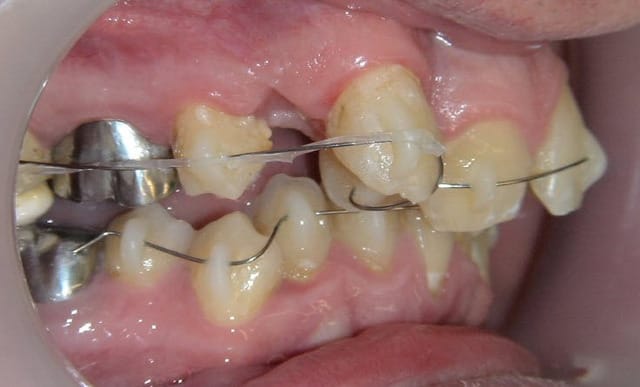

Voici en exemple le cas d’un adulte où la 12 est coincée derrière 11 et 13 etc… (je sais, ploc, j’ai déjà montré il y a quelques temps des photos de ce cas, inutile de me le rappeler gentiment).

14 et 24 sont avulsées.

L’appareillage mis en place est extrêmement simple, des danchamons, le fil NiTi le plus fin qu’on trouve sur le marché (acheté en bobine en « .012 », c’est à dire 0,3mm) et mis en forme avec le manche d’une précelle à la manière d’un bolduc, plus des surélévations molaires en verre-ionomère.

Deux mois plus tard, un élastique très léger est tendu entre les molaires et la canine.

Ci-dessous, photos au départ, le jour de la pose et deux mois plus tard.

Suite du traitement, à quatre mois et sept mois.

A 7 mois, le fil NiTi ultrafin est toujours le même, il n’a pas été remplacé.

Observez l’absence de rotation parasite de 13 et la 12 qui s’est déplacée en vestibulaire !

Remarquez la simplicité du dispositif eu égard aux résultats obtenus.

Reste à reculer un peu l’apex de 13 pour paralléliser sa racine avec les autres et permettre de vestibuler celle de 12. Cela pourra être fait avec des petits accessoires supplémentaires sur un fil un peu plus épais.